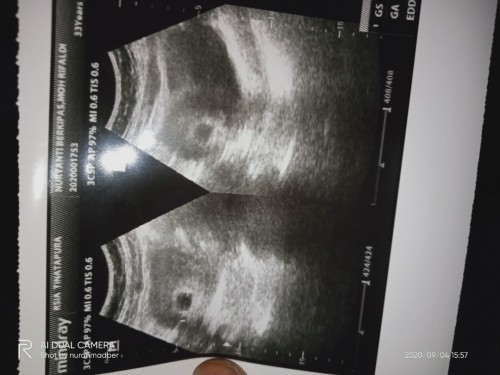

Memang kalo usia janin 5 minggu itu masih kantong yang kelihatan ?

iya bun. tuh buktinya foto usg di atas